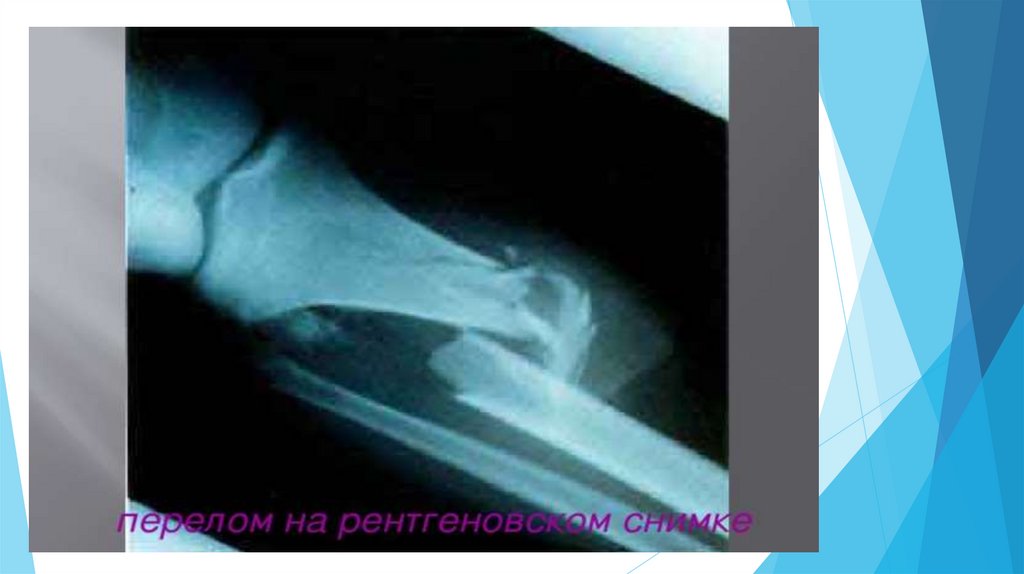

Оказание первой помощи при ушибах, вывихах суставов и переломах костей